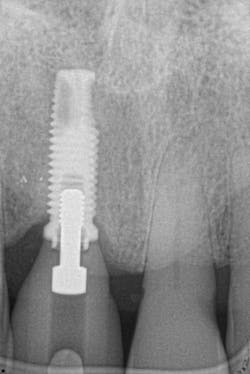

Figures 25 and 26: One-year postsurgery. Clinically all signs of retrograde peri-implantitis have been eliminated and radiographic bone fill can be seen.